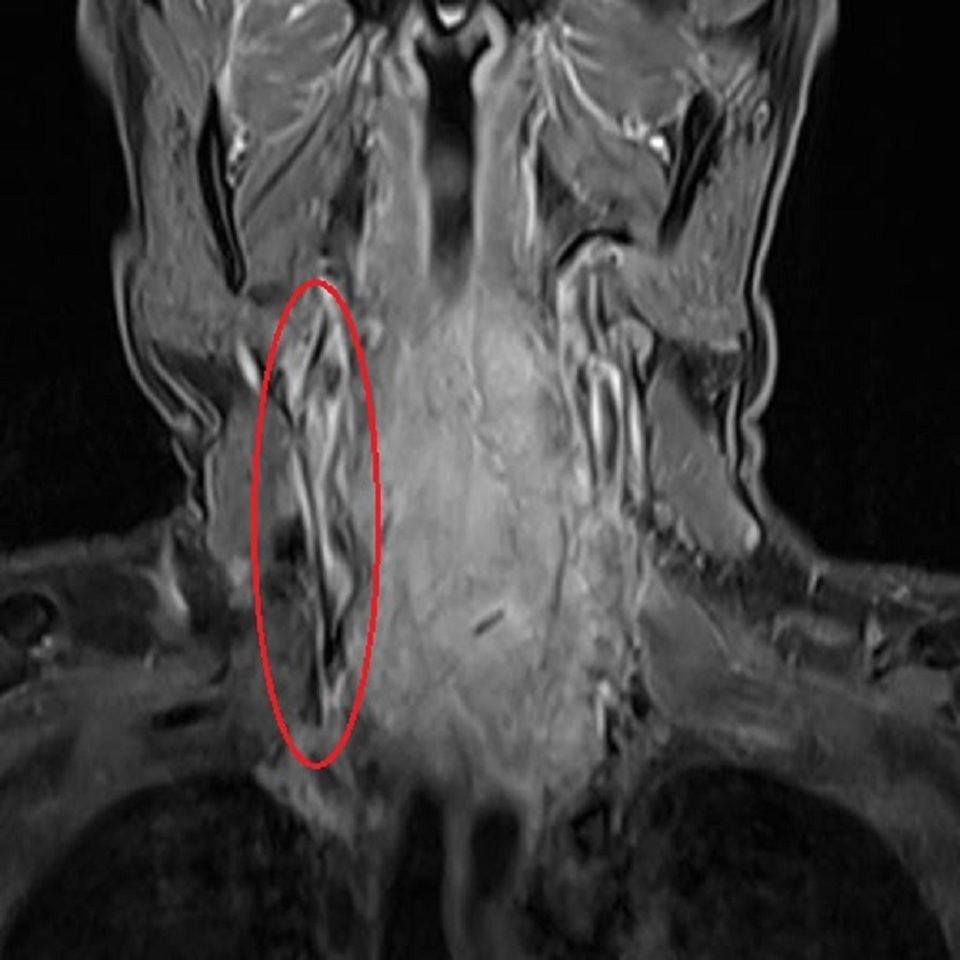

Khối áp xe trên cổ bệnh nhân ghi nhận qua hình ảnh MR

Qua thăm khám và kiểm tra lâm sàng, các bác sĩ phát hiện vùng sau cổ người bệnh có khối áp xe lớn. Thực hiện các xét nghiệm đều cho thấy bệnh nhân bị nhiễm trùng máu nặng. Khai thác bệnh sử của bác sĩ từ phía người nhà bệnh nhân được biết, anh H. bị thoái hóa đốt sống cổ 2 năm nay, điều trị nhiều nơi nhưng không khỏi.

Bác sĩ Lê Thanh Nhàn, khoa Nội Tổng hợp chia sẻ: người bệnh nhập viện trong tình trạng nguy kịch, toàn bộ vùng cổ sưng nề không cử động được, phần mô sau cổ bị áp xe. Sau khi cấy máu, các bác sĩ tìm thấy vi khuẩn Staphylococcus aureus (còn gọi là tụ cầu vàng) đề kháng các kháng sinh thông thường. Đây là loại vi khuẩn có thể xâm nhập vào cơ thể qua các vết thương hay cắt lể. Loại vi khuẩn này, thường gây nhiễm trùng da, niêm mạc và nặng hơn là nhiễm trùng huyết.